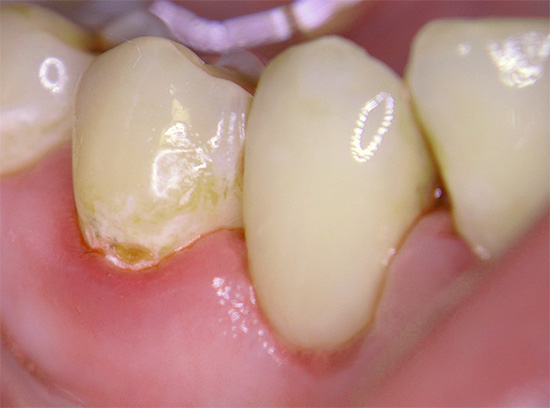

Abaixo estão algumas fotos com exemplos de cárie cervical:

Fotografia cárie primária na área cervical do dente:

Abaixo está uma foto de cárie cervical no estágio local: